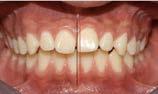

Resultados

Se logró una sonrisa más armoniosa respetando la línea media facial de inicio a final (Figura 13). En la Figura 14 la mejoría en el perfil, con mejor protracción del mentón debido al avance mandibular y como el tercio medio permaneció aumentado de inicio a fin.

En los estudios intarorales finales (Figura 17), se observa la coincidencia de las líneas medias, la resolución del apiñamiento leve, adecuado overjet y overbite y restauración de los laterales microdónticos.

Figura 17. Fotografías intraorales de frente. a) Inicio. b) Progreso. c) Final.